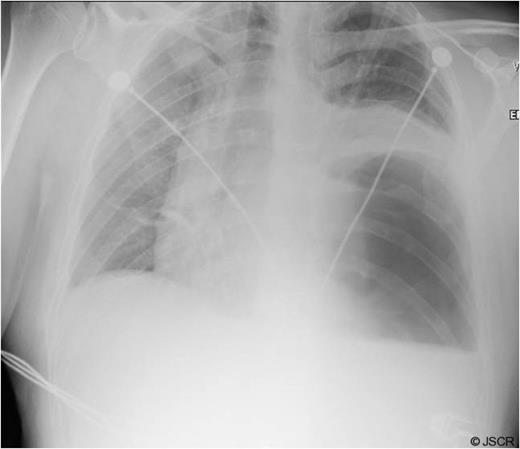

Chest pain persisted and the patient required higher pressure CPAP to maintain adequate oxygenation. Auscultation consistently showed decreased air-entry in the lung bases. On day 3, a repeat chest x-ray showed a left lower lobe collapse above the gastric bubble in the mid zone of the chest (Fig. 4 & 5). CTPA done on the same day to exclude pulmonary embolism confirmed a para-oesophageal hernia that was pushing against the left lung base. Ultrasound scan of the left chest also showed movement of the diaphragm below the gastric bubble.

Chest x-ray on 3rd post-op day showing prominent left sided collapse/ consolidation